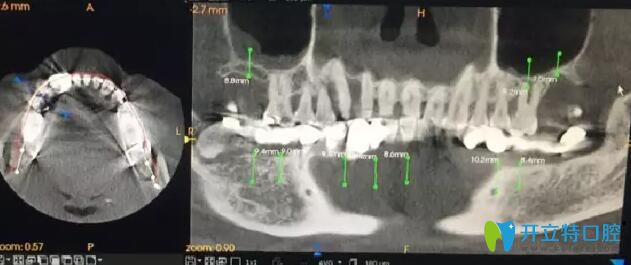

南通摩爾口腔術(shù)前手術(shù)設計

周文清院長根據(jù)王先生的CT判斷,保留33號、34號、35號牙,術(shù)中拔除44號、42號、41號、31號牙。采用數(shù)字化3D導板導航于32號、42號、43號、45號、46號牙位即刻植入5顆ITI種植體。

南通摩爾口腔牙齒種植前檢查

通過術(shù)后CT 對比檢查,與術(shù)前設計幾乎完全一致,實現(xiàn)種植前的設計方案。